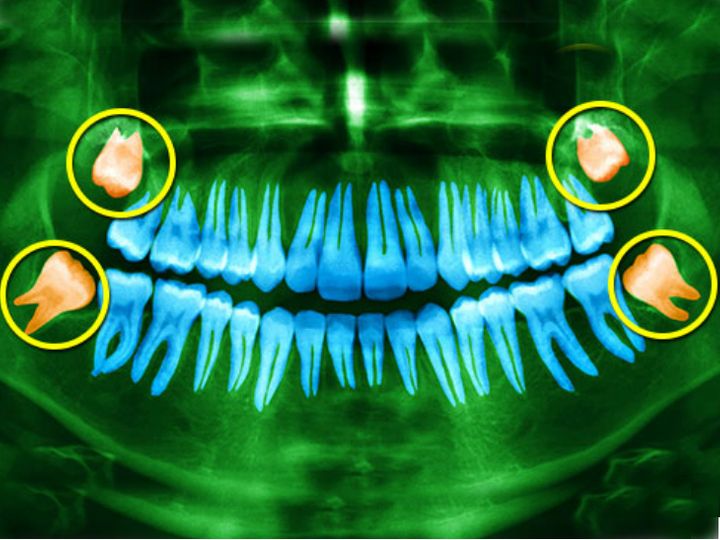

आश्चर्य की बात यह है कि हर तीन में से एक व्यक्ति में ये मीडियन धमनी विलुप्त नहीं होती। बल्कि ऐसे लोगों के शरीर में दो की जगह तीन धमनियां पाई जा रही हैं। हेनबेर्ग का कहना है कि तीसरी धमनी को लेकर अभी यह नहीं कहा जा सकता कि इससे कोई फायदा है। लेकिन, इसका नुकसान भी नहीं है। इसके साथ ही मानवों में अकल दाढ़ विलुप्त होने के कगार पर है।

ऑस्ट्रेलिया के फ्लिंडर्स यूनिवर्सिटी के डॉ. टेघन लुकस का कहना है कि मनुष्य का मुंह छोटा होता जा रहा है। ऐसे में अकल दाढ़ के लिए जगह नहीं बच रही है। खान-पान में बदलाव से भी यह विलुप्त हो रही है।